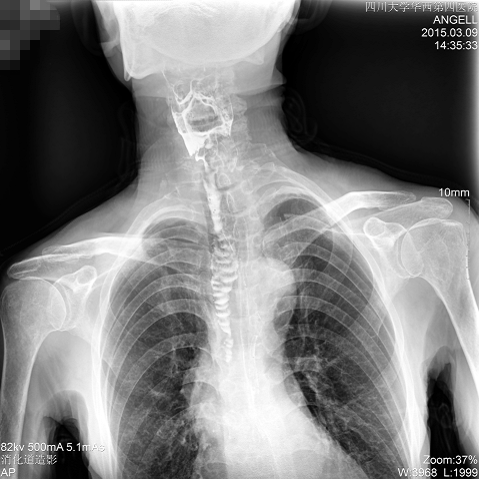

如下圖所示:該患者因吞咽時感到很難受,進食時也經常咳嗽故就醫診斷。使用多功能dr為病人進行消化道造影診斷,要求他吞鋇后發現,食道各段通過順利,形態規則,雙側梨狀窩不對稱左側稍淺,多次吞咽動作后,仍見鋇劑滯留,并見鋇劑進入氣管,屬于會厭征陽性。會厭功能紊亂,鋇劑進入了氣管。

圖為正位:通過動態影像可以清楚看到鋇劑進入了支氣管道且雙側梨狀窩不對稱

通過多功能dr可以診斷該病人的癥狀為會厭功能紊亂,鋇劑進入到了氣管。而在動態透視下可以清晰的觀察到鋇劑從何處進入氣管,可清晰顯示食管粘膜結構。使用多功能dr其獨特的視頻采集技術,可實時保存視頻并能實現900萬像素實時點片,才能獲取這樣清晰的病灶點。而常規dr只能拍攝靜態片,且成像效果大打折扣,因此較難確診病灶。